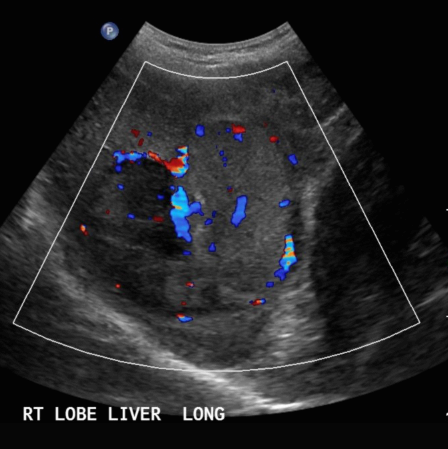

- color doppler : internal mass pattern (feeding artery)

- color doppler: basket pattern